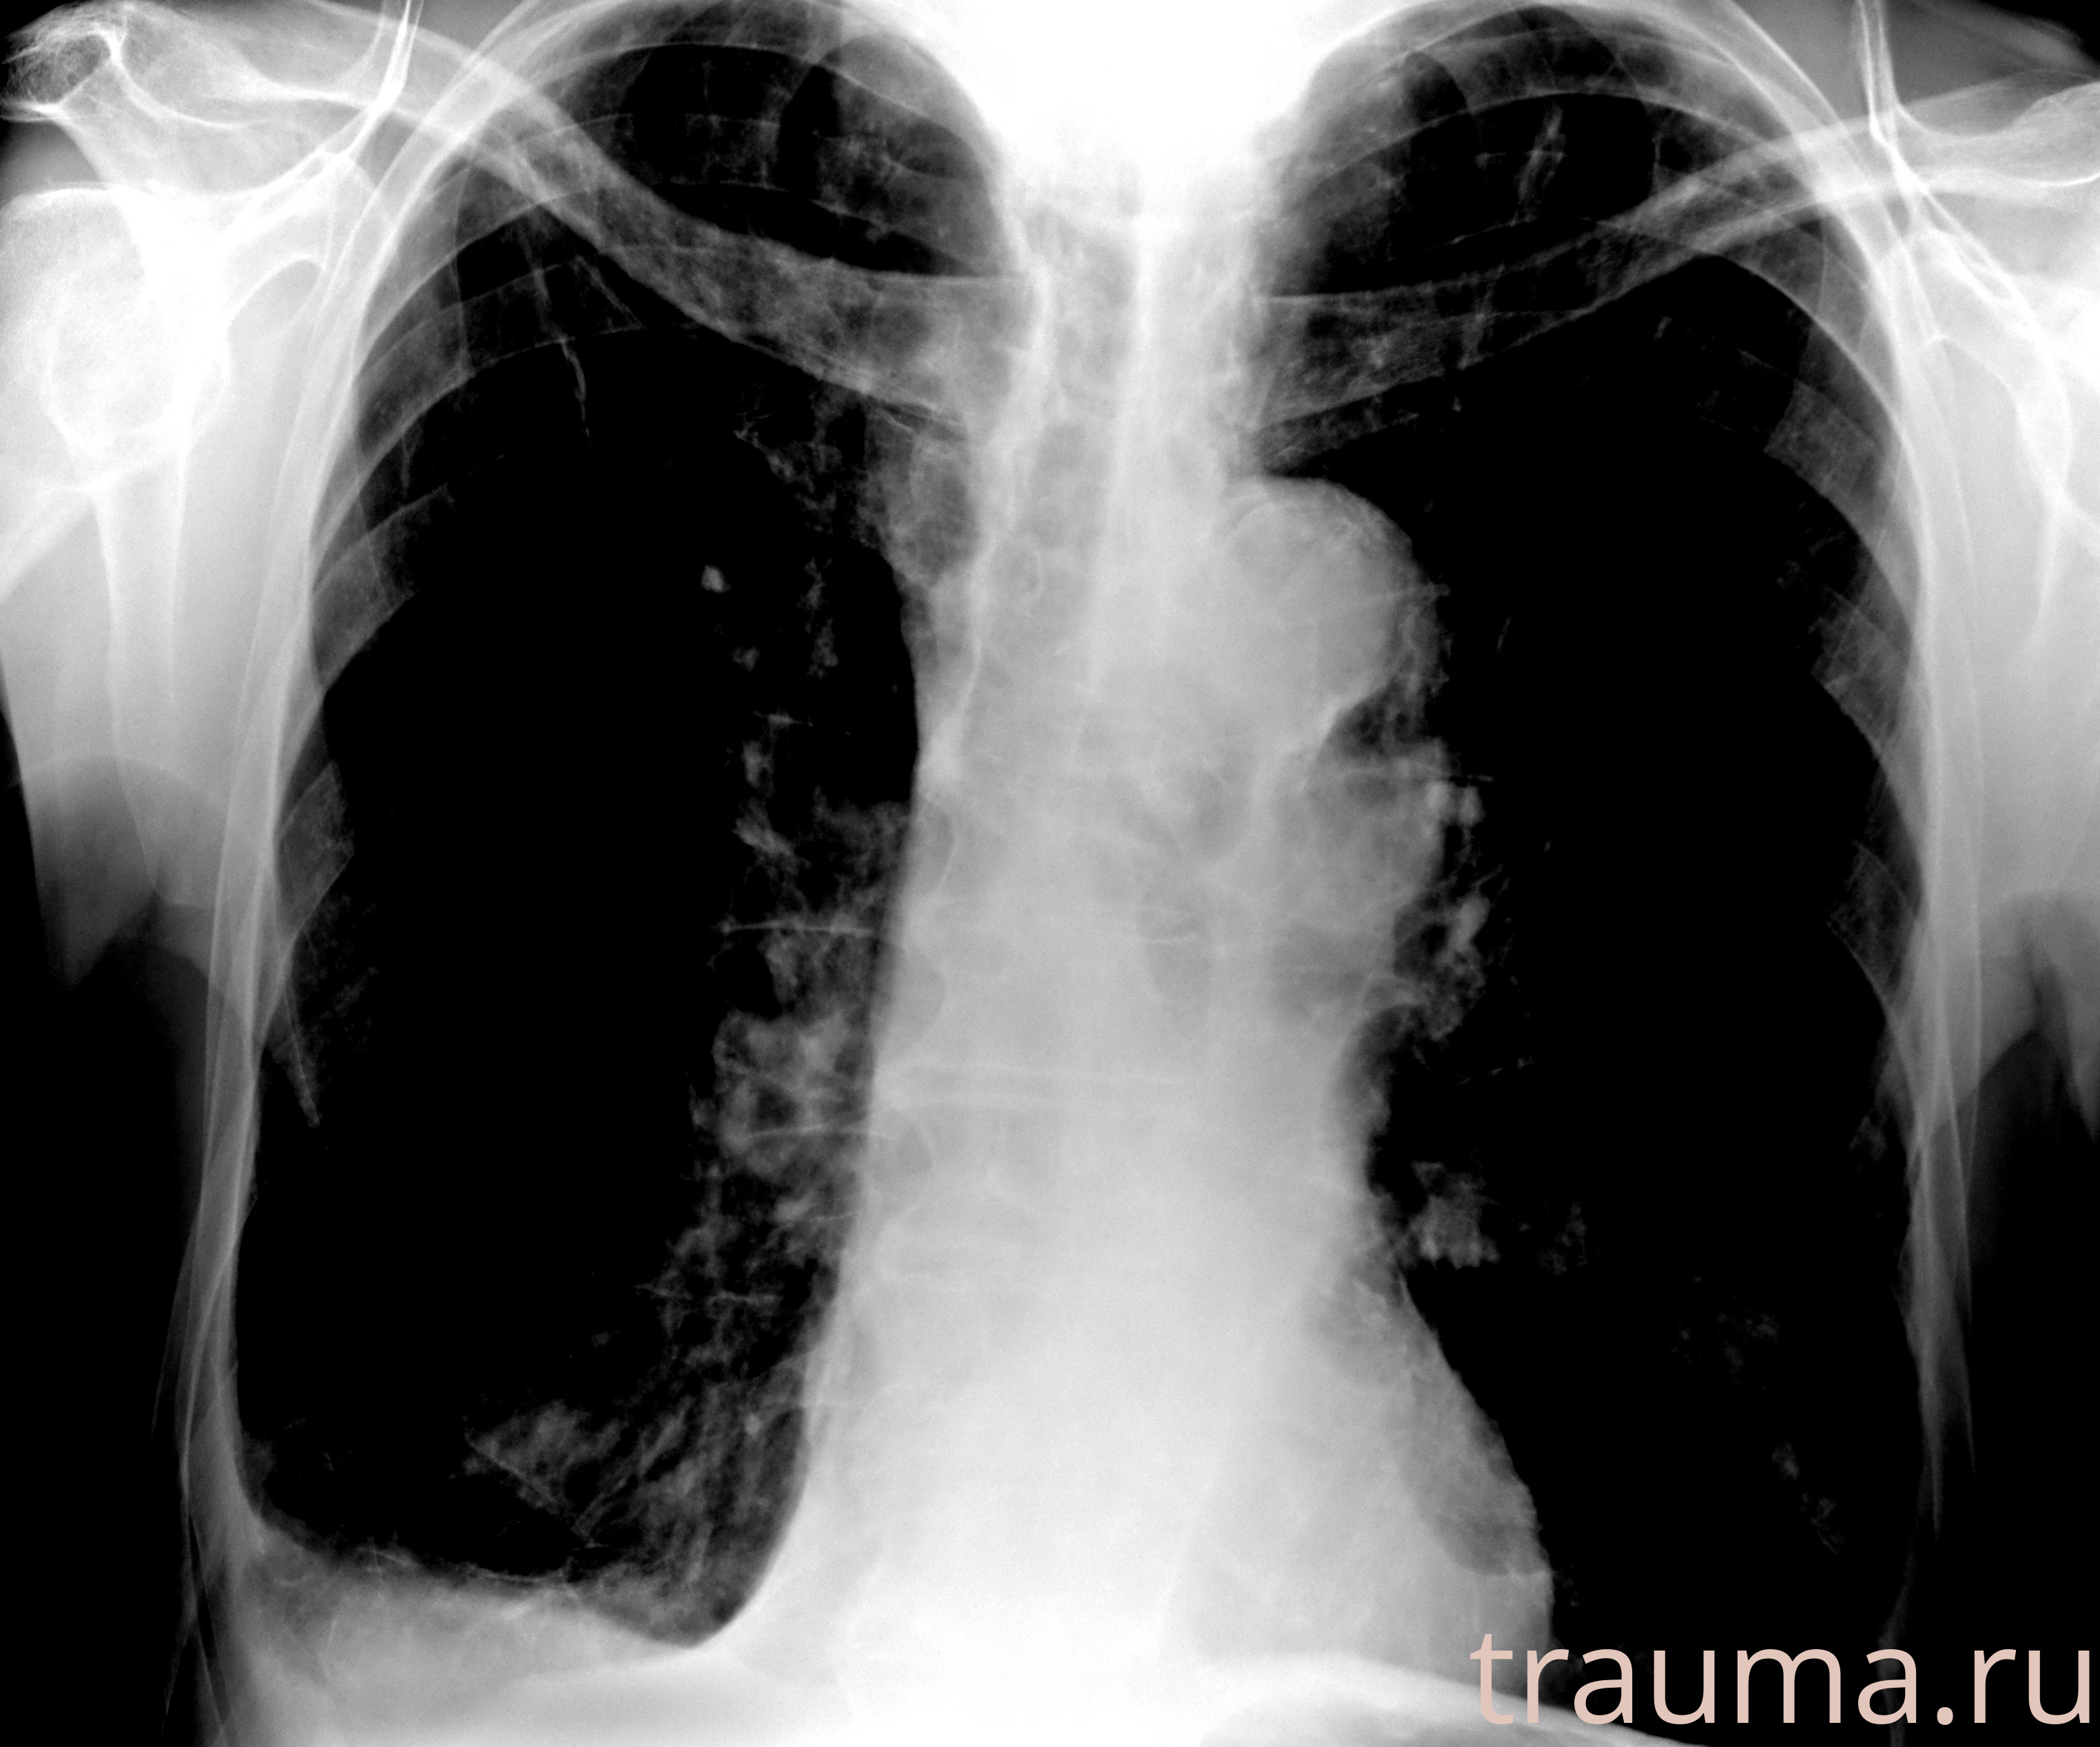

Рентгенограммы

Рентген на дому: по вашему адресу приезжает врач-рентгенолог, травматолог-ортопед с мобильным рентгеновским аппаратом, проводит диагностику травмы или заболевания, делает необходимые рентгенограммы, дает рекомендации по дальнейшему лечению. Получить качественные снимки в домашних условиях возможно благодаря уникальной методике, разработанной МосРентген Центром для института  Склифосовского